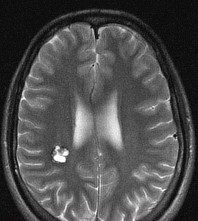

- Краткая информация о пациенте. Пациент К., 19 лет, курсант ВВУЗа. В течение последнего года беспокоили кратковременные приступы дезориентации, что расценено как фокальные приступы с нарушением сознания. За медицинской помощью не обращался до конца августа, когда на фоне полного благополучия появилась интенсивная головная боль. Осмотрен неврологом, рекомендовано выполнение МРТ головного мозга, по данным которого выявлена кавернозная мальформация правой теменной доли с признаками подострого кровоизлияния. Для дальнейшего лечения и обследования госпитализирован в клинику нейрохирургии ВМедА. По данным МРТ головного мозга от 06.09.2021 г.: определяется кавернозная мальформация правой теменной доли, прилежащая к зоне центральных извилин с признаками подострого кровоизлияния общими размерами 2.0х1.5х1.7 см.

МРТ головного мозга: кавернозная мальформация правой теменной доли с признаками кровоизлияния